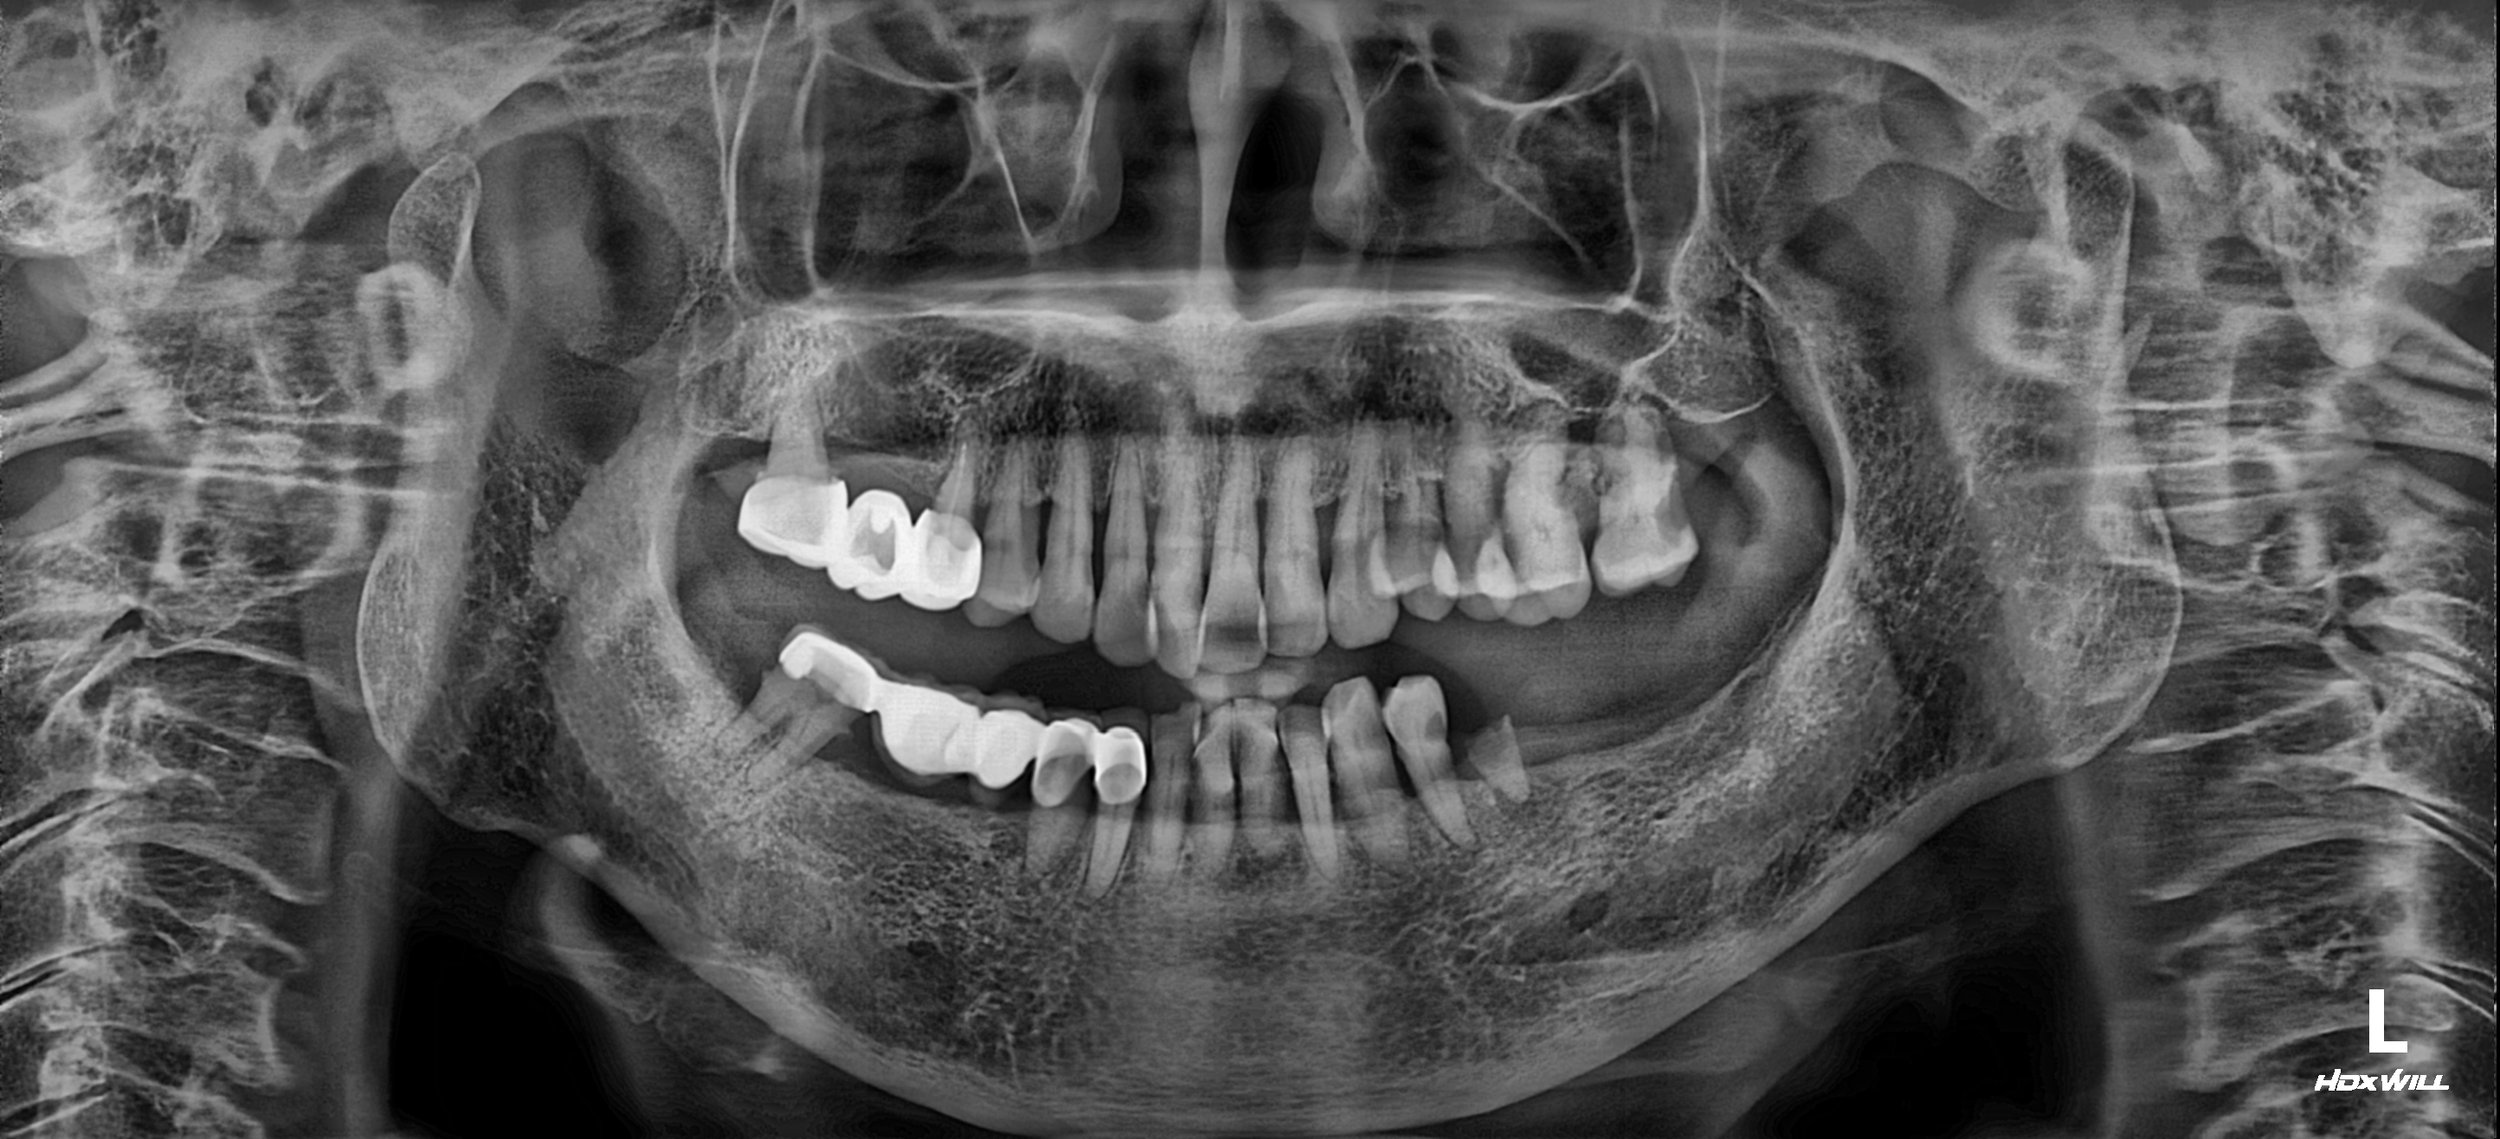

• Pre-operative Radiograph (OPG) OPG showing multiple missing teeth, failing bridge abutments, and severe horizontal bone loss.

OPG - BEFORE